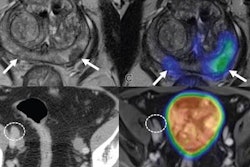

Imaging software developer Syntermed highlighted that it will be the first distributor in the U.S. of Pylarify AI, Lantheus Medical Imaging's artificial intelligence (AI) program for assisting standardized quantification of prostate-specific membrane antigen (PSMA)-PET/CT scans.

Lantheus received approval from the U.S. Food and Drug Administration (FDA) in May 2021 for Pylarify (F-18 DCFPyL), a PET radiotracer that targets PSMA, with clearance for Pylarify AI following in July.

Pylarify AI uses a deep-learning algorithm that has been trained and validated on more than 3,000 images. It allows healthcare professionals and researchers to perform standardized quantitative assessment of PSMA-PET/CT images.

PSMA is a protein expressed on prostate cancer cells. Imaging and quantifying PSMA in patients with suspected prostate cancer can help clinicians determine effective treatment approaches.